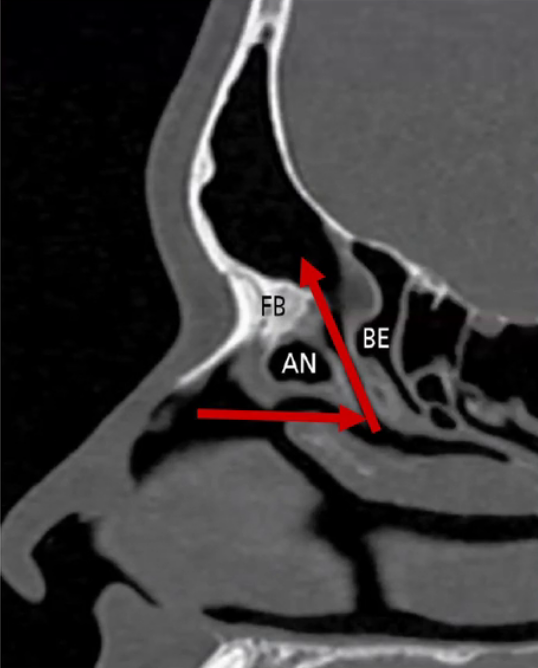

Qual o nome da estrutura apontada abaixo e ela é limite de qual região?

ARTÉRIA ETMOIDAL ANTERIOR

• FORMA O LIMITE PÓSTERO-INFERIOR DO RECESSO DO FRONTAL (no teto do etmóide).

• Sai da órbita pelo canal ósseo e vai em direção á lamela lateral da lâmina cribiforme.

Todo cuidado deve ser tomado com a artéria etmoidal anterior medialmente, porque as paredes ósseas ali são muito finas e a dura-máter muito aderida a elas (risco de fístula). E o limite lateral do canal ósseo dela penetra na órbita (risco de lesar lamina papirácea).